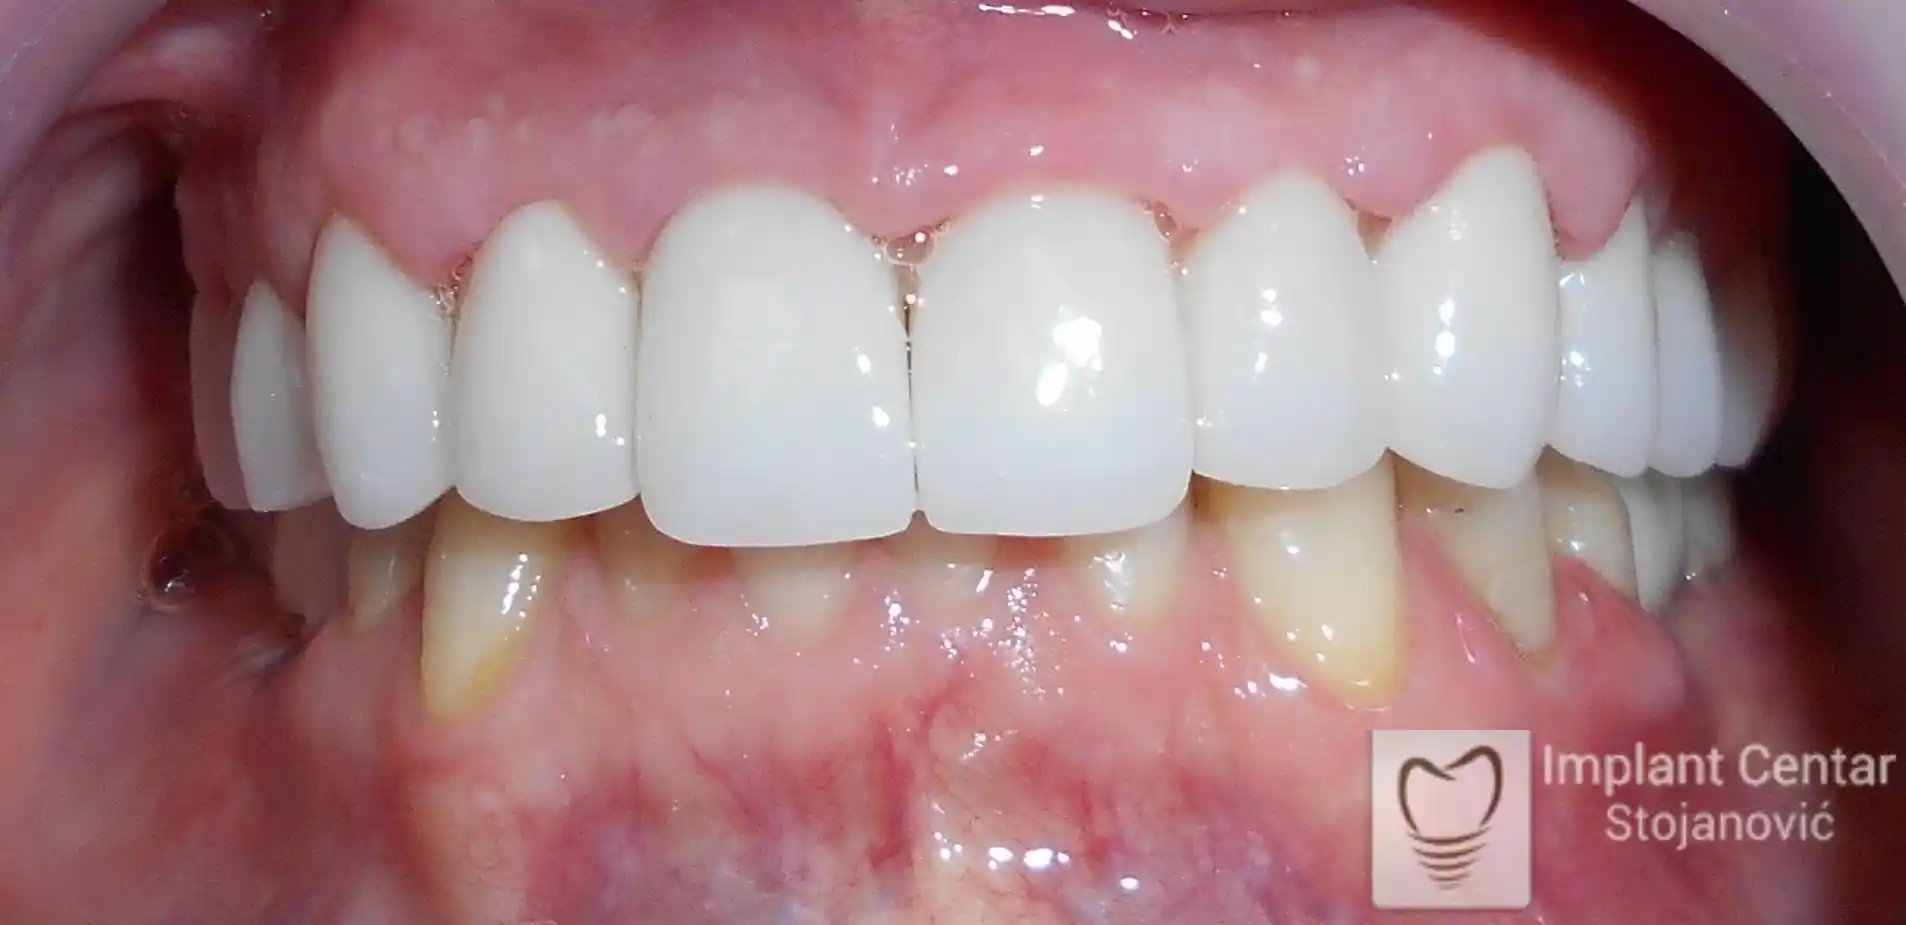

Pacijent je došao sa starim, dotrajalim mostovima koji nisu pružali adekvatno samopouzdanje niti estetski izgled. Nakon detaljnog kliničkog pregleda i analize, izrađen je plan terapije koji je podrazumevao skidanje postojećih mostova i vađenje zuba koji nisu mogli da pruže podršku novom fiksnom protetskom radu.

Ugradnjom optimalnog broja implantata obezbeđena je dugotrajna stabilnost protetskog rada i pravilan raspored sila pri žvakanju. Definitivne cirkonijum-keramičke krunice omogućile su maksimalnu estetiku, funkciju i vraćeno samopouzdanje pacijenta.